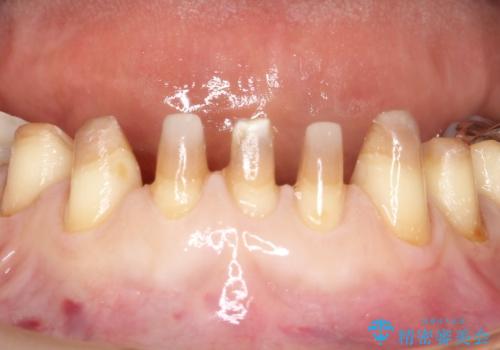

- 昔、他院で治療したダイレクトボンディング(歯の表面にだけ白い材料を盛る治療)のやりかえを主訴に来院されました。叢生の改善も同時に行うためにオールセラミッククラウンにより治療を行いました。

ダイレクトボンディングでの治療より、天然歯に近い見た目を再現することができます。